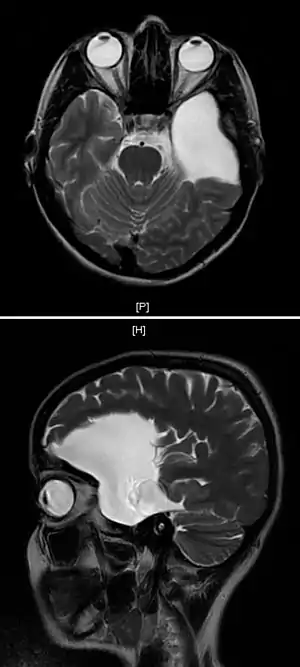

Cisto aracnoide

Cisto aracnoide é uma lesão congênita na membrana aracnoide que se expande com as secreções do líquido cefalorraquidiano. Corresponde aproximadamente a 1% de todas as lesões intracraniais nos adultos e a 3% nas crianças. Na distribuição do sexo é proeminente nos homens na relação de 3:1.

É um saco de líquido na membrana aracnóide que cobre o cérebro e a medula espinal. Há três membranas que cobrem as partes do sistema nervoso central: a dura-máter, a aracnoide e a pia-máter. Os cistos aracnoides aparecem na membrana aracnoide (espaço subaracnoide). Os lugares mais comuns dos cistos aracnoides intracraniais são na fossa média (perto do lobo temporal), na região da sela túrcica (perto do terceiro ventrículo) e na fossa posterior, com o cerebelo, o ponte, e a medula oblonga.

Os cistos aracnoides podem aparecer secundariamente a outras doenças como a síndrome de Marfan, aracnoidite, agenesis do corpo caloso. O diagnóstico do cisto aracnoide é freqüentemente acidental, principalmente durante o exame de pessoas com tonturas. Os cistos aracnoides são facilmente vistos nos exames de tomografia e na ressonância magnética da cabeça.